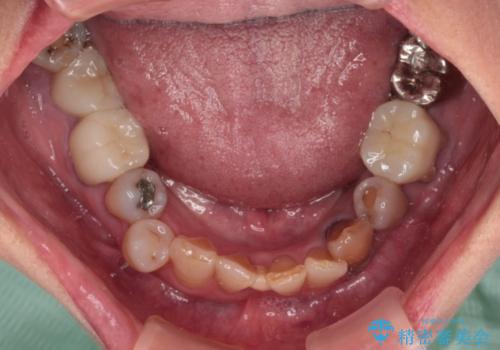

- 長年気にしていた捻れた前歯が欠けたとのことで来院された患者様です。

矯正治療に抵抗があったそうですが、前歯が欠けたことをきっかけに、矯正治療で歯列を整えた上で、セラミッククラウン治療を行う決心が付いたとのことでした。

デコボコが強いため、ブリッジや残根となっている部分のスペースを利用して歯列を整え、変色や欠けている歯をオールセラミッククラウンによる補綴治療を行うこととしました。